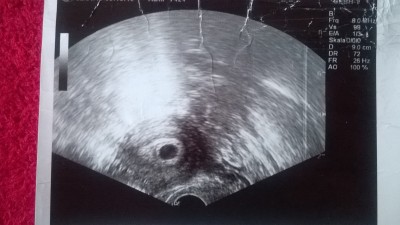

Jetzt mit Luca war es eine Ems keine Blutungen nichts laut gyn 6+0 bilderbuch ss

8+5 Diagnose ma aaaaber hcg bei 57000

Dateianhänge

6+0